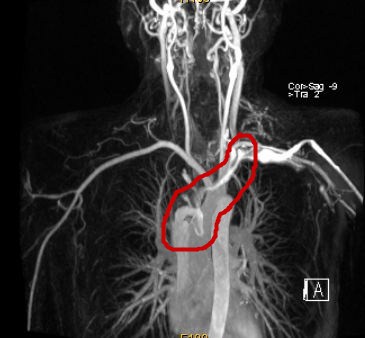

術後MRI影像,人工血管正常運作

腫瘤阻塞了上腔靜脈,血流受阻,造影不能顯現

該院檢查發現腫瘤將近10cm大小,已經侵犯上腔靜脈,上腔靜脈、雙側頭臂靜脈及右側頸內靜脈內已經有癌栓並血栓形成,上腔靜脈已經無法通過影像看到,正是這些栓子導致張先生出現了頭暈、臉腫等上腔靜脈阻塞的癥狀。深圳市二醫院胸外科主任錢有輝教授仔細分析病情後指出,本例患者主要問題在於患者的胸腺瘤已經出現了大血管侵犯,手術需要完整切除腫瘤之外還需要對部分大血管進行切除並置換人工血管,這樣才能達到斬草除根的效果。